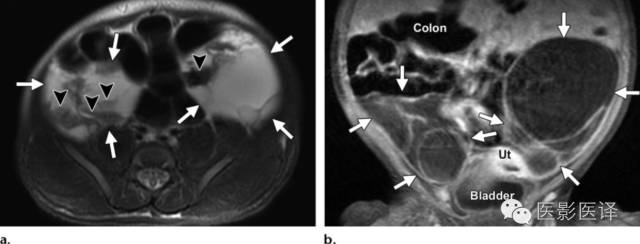

超声检查中,复杂性卵巢囊肿是厚壁的,且回声不均质。图像特征包括多个分隔(图4、5)、内部移动性高回声、实性表现(图6),或液液平面(图5、7)。复杂性囊肿被认为是扭转的结果,胎儿比新生儿更常发生。出现复杂性囊肿的表现高度提示需要手术。与胎儿卵巢囊肿伴发的其他影像表现包括羊水过多和腹水,可能是由于漏出或囊肿破裂所致。肠管或肾脏的继发梗阻被认为是扭转时卵巢坏死引起的粘连所致。

图5.双侧出血性新生儿卵巢囊肿。新生儿MR图像用于评估在外院胎儿超声中发现的两个实性腹内占位。(a)轴位脂肪饱和T2WI MR图像显示双侧多房的附件占位(a和b箭),伴有液液平面(箭头),提示出血。(b)冠状位脂肪饱和T1WI增强MR成像显示双侧占位无实性成分(箭)。多囊占位独立于结肠、肝脏、脾脏和肾脏,在膀胱上方。双侧病变均位于中线外侧。强化的子宫(Ut)在膀胱上方。